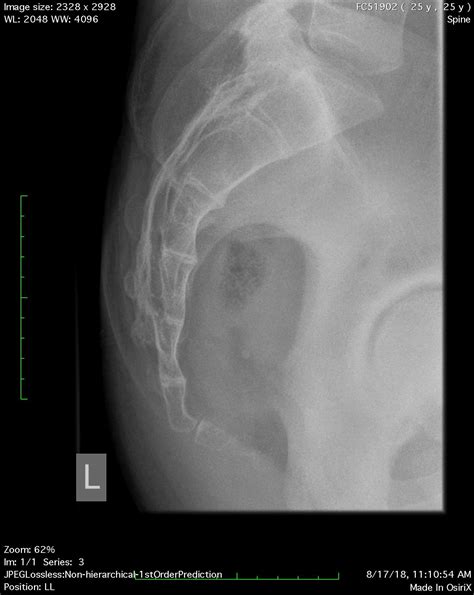

The Procedure of Sacrum Coccyx X Ray

The Sacrum Coccyx X Ray procedure is generally quick and painless. Here is a step-by-step overview of what to expect:

1. The patient will be asked to lie down on an X-ray table, usually on their back or side.

2. The radiographer will position the X-ray machine to capture images of the sacrum and coccyx.

3. The patient may be asked to hold their breath briefly to minimize movement and ensure clear images.

4. Multiple images may be taken from different angles to provide a comprehensive view of the area.

5. The entire procedure typically takes about 15-30 minutes.